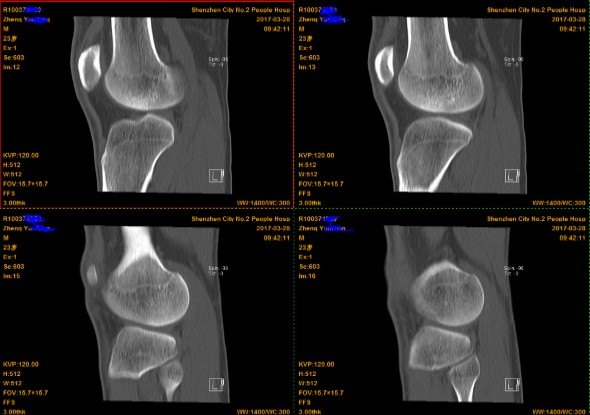

2.CT(以膝关节为例)

由于CT 是三维成像,包括矢状面,冠状面和横断面三个层面的扫描。一张CT片子也是包括医院、姓名、性别、年龄、检查日期、侧别、扫描序列等信息的。

矢状面---是从前向后、从内往外扫描成像。

冠状面---是从内向外、从前往后扫描成像。

横断面---是从上向下、从前往后扫描成像。